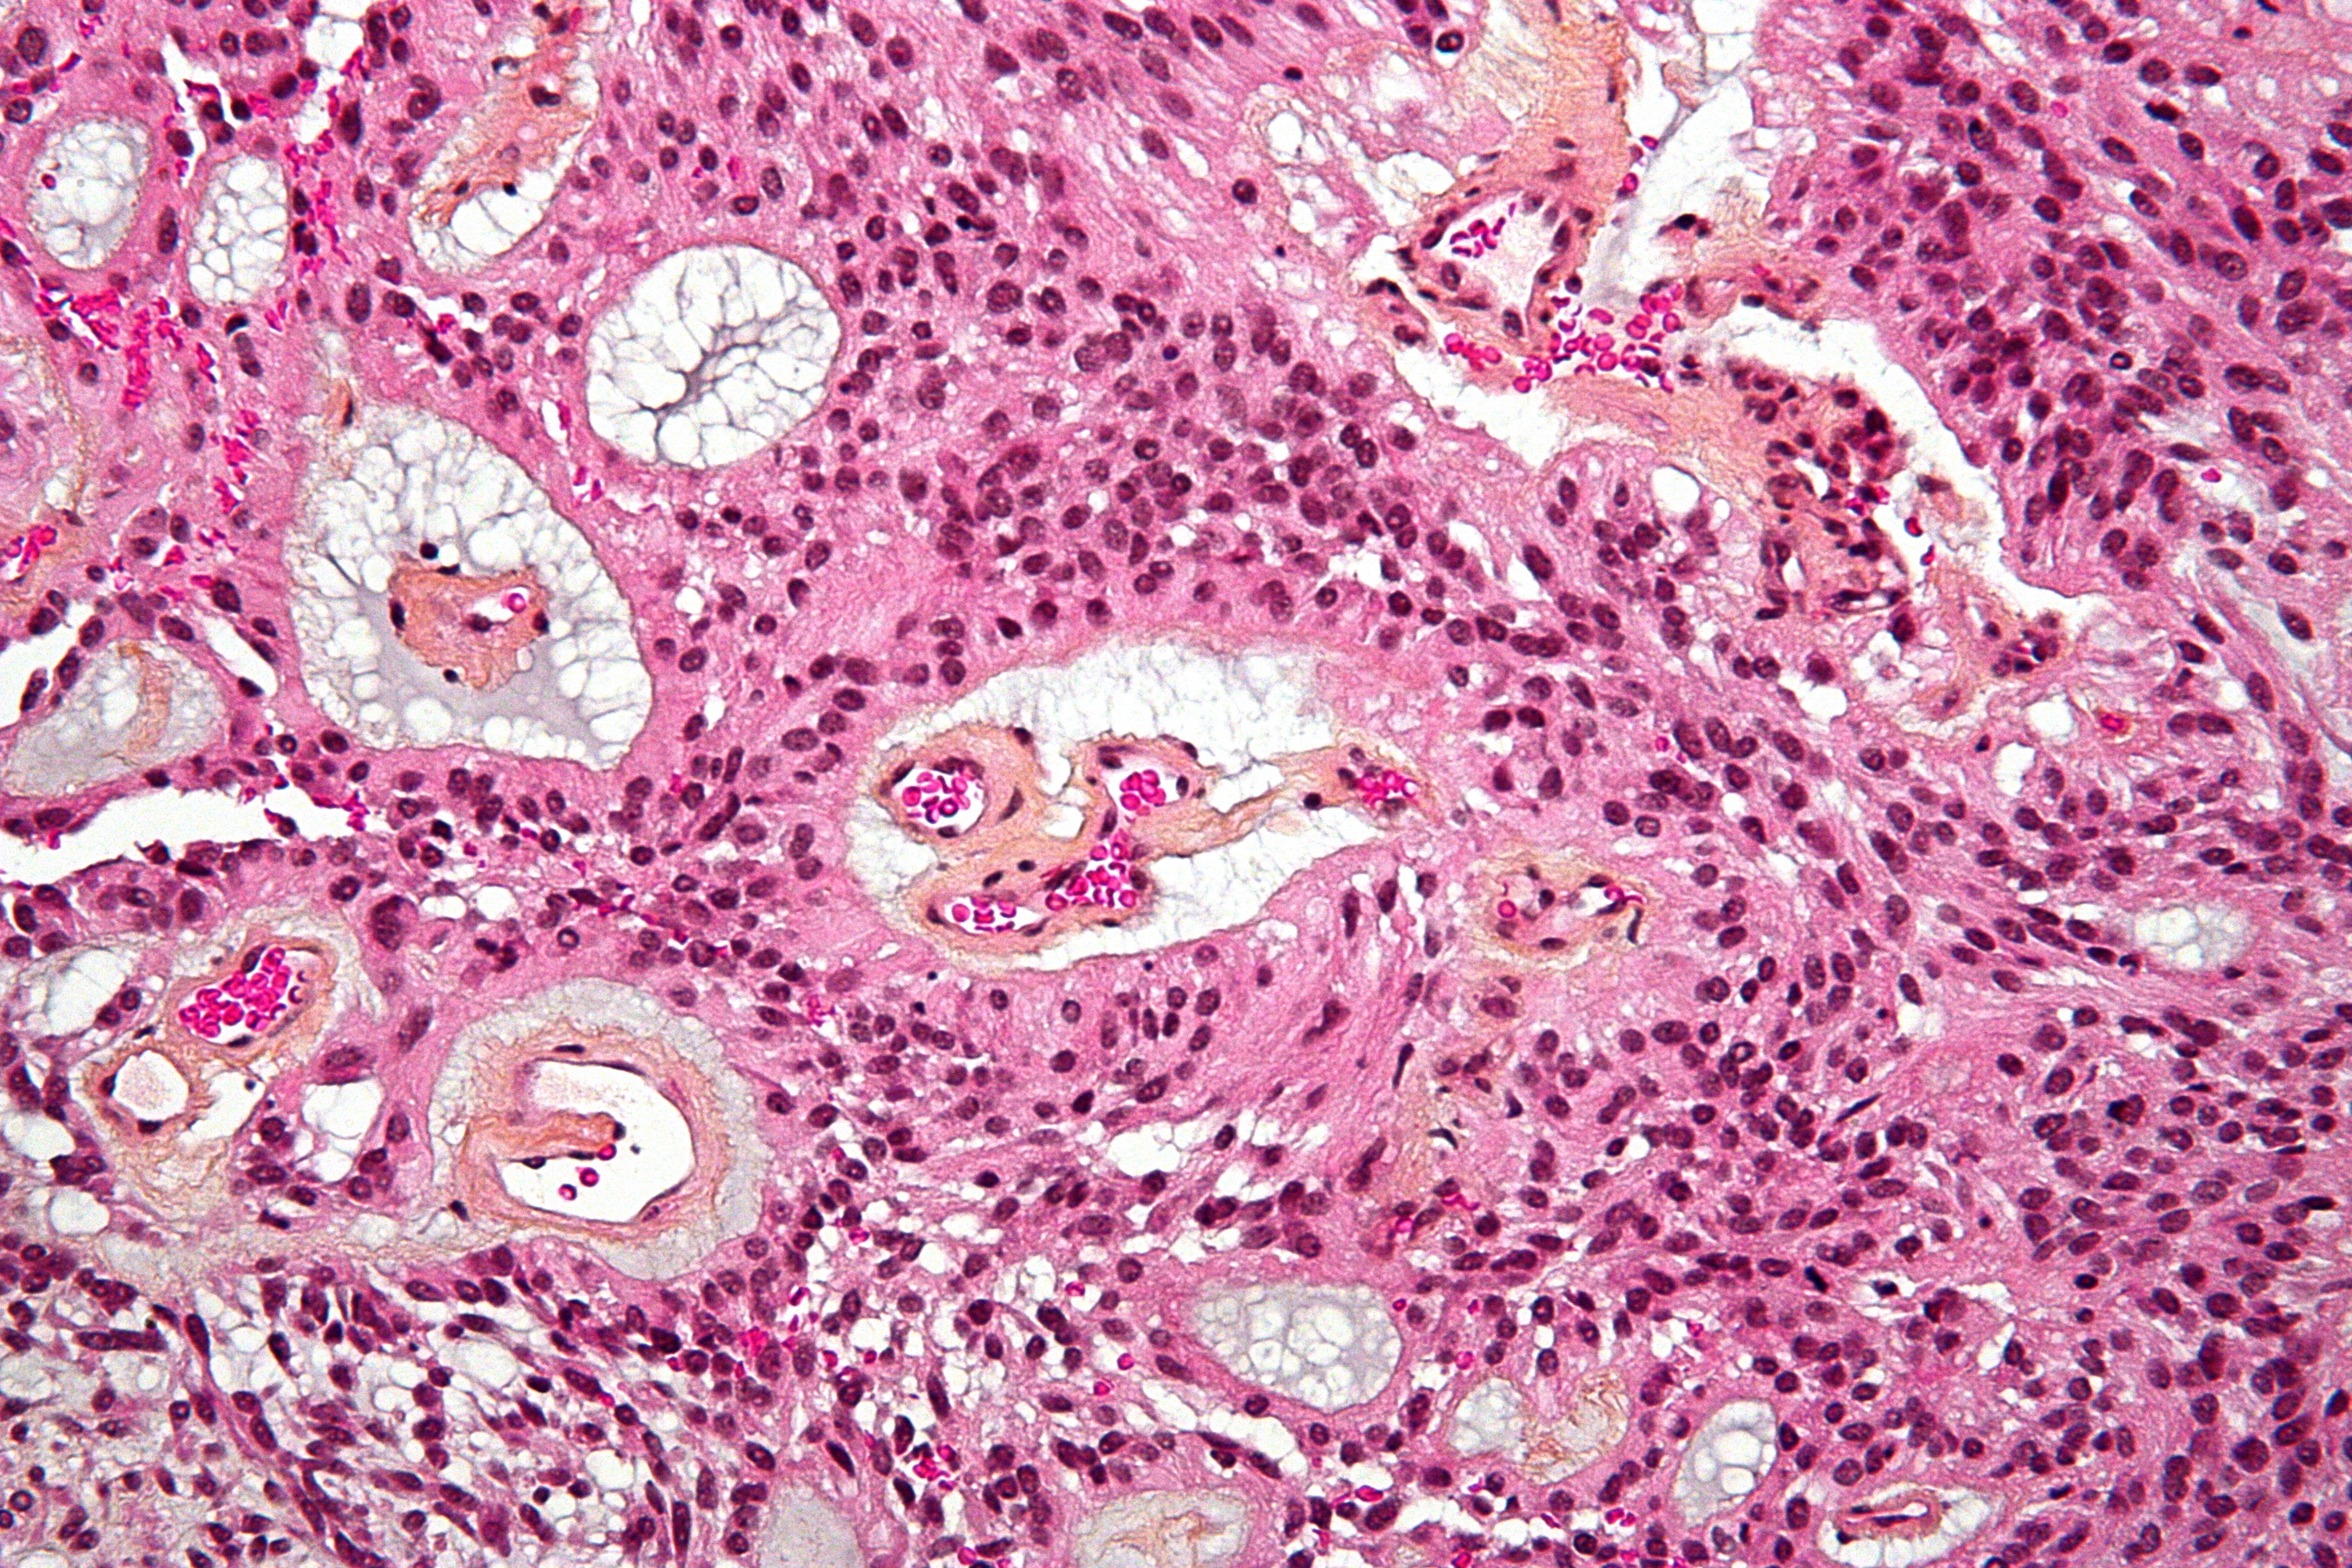

Ependymoma accounts for less than 2% of all adult brain tumors. Rosette formation is a hallmark of ependymoma with increased cellularity, cytological atypia and microvascular proliferation which suggests ependymoma.